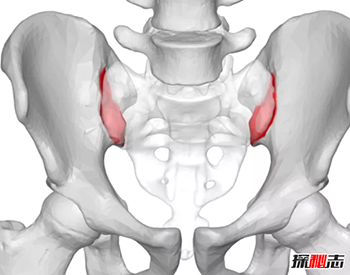

10、出生时骨盆骨

人骨为什么那么可怕-人体骨骼的十大疯狂事实490 / 作者:网上的人生 / 帖子ID:52913

怀孕期间,女性的身体发生了很大的变化。骨盆关节有一些骨骼适应影响松弛。一种名为松弛素的激素对女性子宫颈和骨盆肌肉、韧带和关节都有重要作用。由于松弛素,骨盆关节在分娩期间变得更有弹性。研究发现,女运动员前交叉韧带损伤率较高。随着松弛素水平的升高,骨盆不稳定和关节无力。